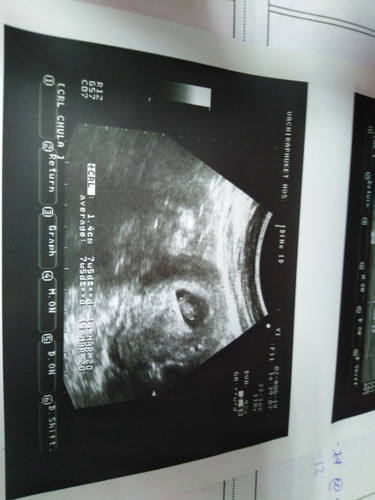

ลูกน้องของฉันดีใจมากเลยลูกคนที่2ของบ้าน

8สัปดาห์ลูุกน้อย